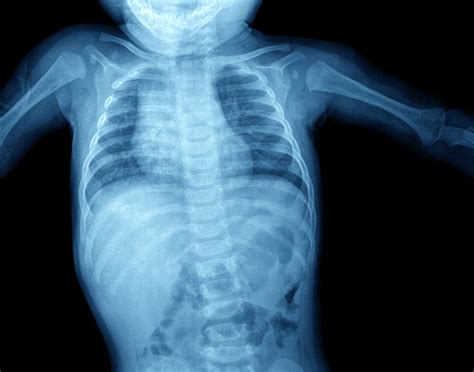

In the realm of medical diagnostics, the Belly X Ray stands as a cornerstone tool for evaluating abdominal conditions. This non-invasive imaging technique provides valuable insights into the internal structures of the abdomen, aiding in the diagnosis and treatment of various medical issues. Understanding the intricacies of a Belly X Ray can empower patients and healthcare providers alike, ensuring better outcomes and informed decision-making.

A Belly X Ray, also known as an abdominal X-ray, is a type of radiography that uses low doses of ionizing radiation to produce images of the internal structures of the abdomen. These images help healthcare professionals identify abnormalities, such as blockages, fractures, or foreign objects, that may not be visible through physical examination alone.